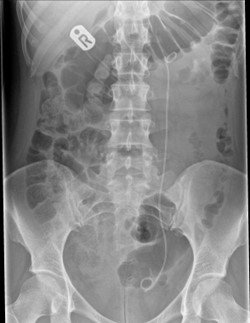

A ureteric stent is a hollow tube which runs the length of the ureter from the kidney to the bladder. It is made of a flexible plastic material and usually measures between 22 and 26 centimetres.

The stent is held in place by a coil at the top within the kidney and a coil at the bottom within the bladder. The stent is flexible and moves with any body movements.

This is usually placed in the ureter under a general anaesthetic (while you are asleep). A telescope (cystoscope) is passed through the urethra into the bladder. The stent is placed over a wire into the ureter and kidney via the opening of the ureter in the bladder. The stent may also be inserted as an additional part of an operation on the ureter and kidney (ureteroscopy). Occasionally it may be inserted via the kidney, under local anaesthetic, using special X-ray techniques.

The stent is checked to be in the correct position by taking an X-ray at the end of the procedure or occasionally after the procedure.